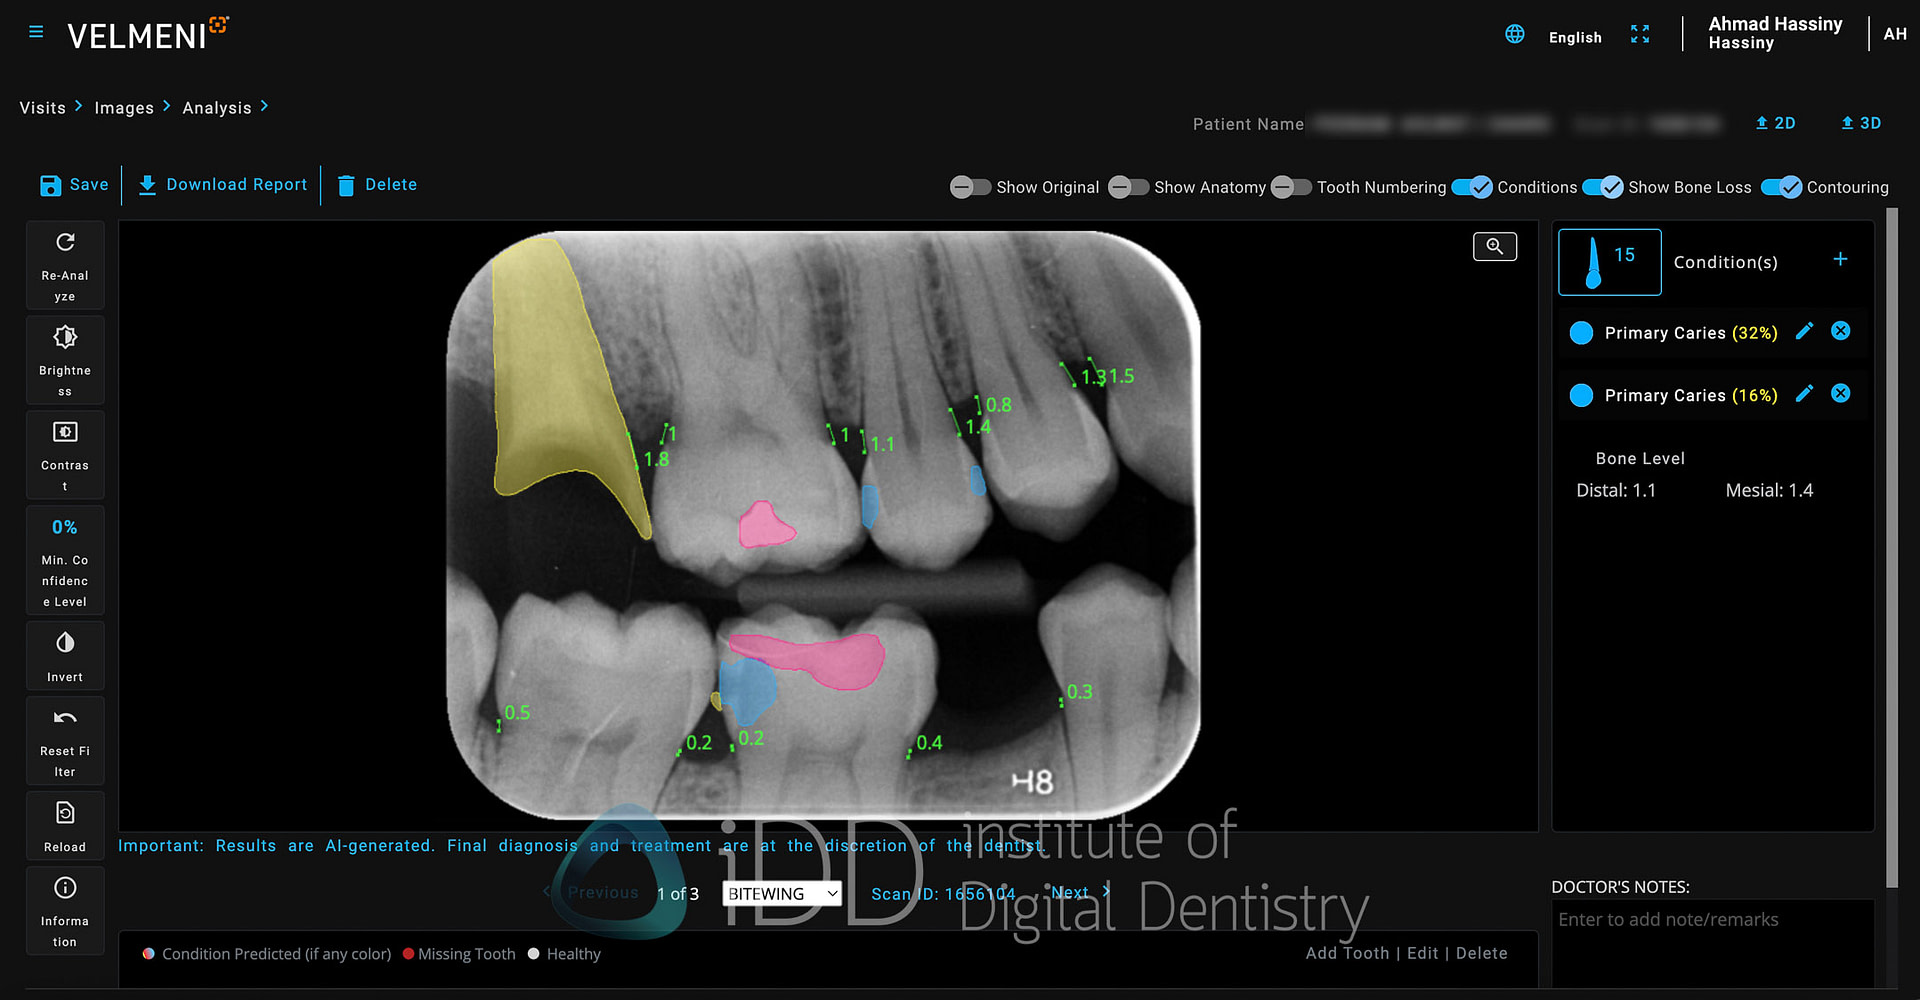

Navigation within the platform feels mostly intuitive, if somewhat utilitarian. The image viewer occupies most of the screen real estate, with AI detection controls arranged in a toolbar along the top with simple on and off toggles. A side panel includes standard image manipulation tools - brightness, contrast, and zoom controls etc.

The software automatically segments each x-ray into tooth numbers. Each type of detection (caries, bone loss, etc.) can be toggled individually by hovering over it, preventing the screen from becoming cluttered with markings. There is also a colour-coded summary at the bottom that indicates what detection has been found for each tooth.

When you click on any tooth, the window on the right provides additional details about the finding, including measurement data and confidence levels. The ability to edit or dismiss AI findings is straightforward, acknowledging that professional judgment should always take precedence over automated detections.

One of Second Dentist's useful features is its ability to toggle between different visualization styles for AI findings. The platform offers two display modes: contour shading and box indicators. The contour shading option, which I find far more effective, fills in detected areas with semi-transparent colors that follow the natural contours of the findings. This creates a cleaner, more intuitive visualization that makes it easier to understand the extent and shape of detected pathologies.

Second Dentist takes a straightforward approach to caries detection with a simple marking system. The platform uses a single color - blue - to highlight areas of suspected decay, whether it's primary caries in untreated teeth or secondary caries around existing restorations. The blue markers clearly stand out against the grayscale of the radiograph, drawing attention to suspicious areas that warrant closer examination.

Second Dentist's approach to bone level assessment uses a straightforward two-color system paired with automated measurements to streamline the detection of bone loss.

The platform keeps things simple with a two color-coding system: green lines indicate healthy bone levels (up to 2.5mm from CEJ), while pink lines signal potential bone loss (anything exceeding 2.0mm). This clear visual distinction makes it easy to spot areas requiring attention at a glance.

Second Dentist uses yellow indicators to highlight areas where radiographic calculus is detected. The AI analyzes radiographs for the characteristic appearance of calculus - those radiopaque deposits along root surfaces - and marks them for easy identification.

Second Dentist uses a two-color system for marking existing dental restorations on radiographs. Fixed prosthetics like crowns and bridges are highlighted in yellow, while direct restorations such as composite or amalgam fillings are marked in pink.